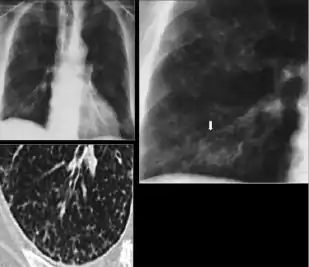

Dense homogenous opacity in right, middle and lower lobe of primary pulmonary TB.

Chest x-ray showing patchy opacification on the upper right and mid-zone lung with fibrotic shadows, as well as bilateral hilar lymphadenopathy.

Chest x-ray showing coarse reticulonodular densities on the lower right lung of post-primary pulmonary TB.

Chest x-ray of Ghon's complex of active tuberculosis